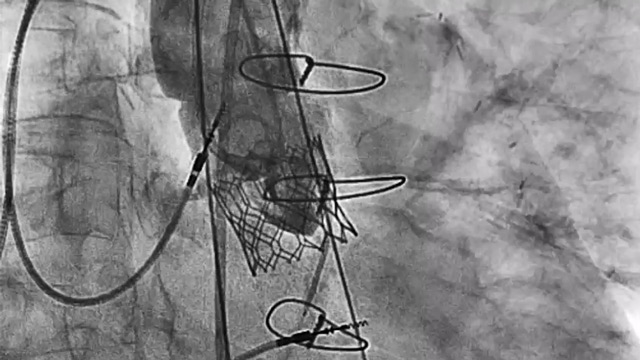

Supported by an unrestricted educational grant from Boston Scientific

A 78-year-old woman with atrial fibrillation and obesity (BMI 34.3), normal left ventricular function, CHADS-VASCs 5 and HAS-BLED 4, presented with severe gastrointestinal bleeding.

She underwent implantation of a Watchman FLX™ pro under local anesthesia via two right femoral...